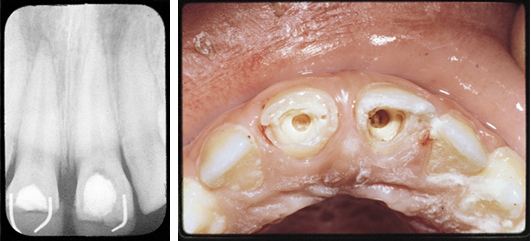

Case 2

The patient presented in pain with fractured upper central incisors and exposed pulps. Pulpotomies were performed using Pulpdent Paste as the pulpal dressing, which was sealed in place with zinc phosphate cement. Composite restorations were placed using pins for retention. One year after the pulpotomies, the patient returned for more esthetic composite restorations.

A radiograph taken after one-year shows two new dense dentin bridges with composites held in place with pins.

Fig. 1: This is a rare photograph of the new dentin bridges after removal of the composite, pins and zinc phosphate cement.

Fig. 2: Multi-Cal can also be used for dentin bridge formation in direct pulp capping, pulpal curettage and vital calcium hydroxide pulpotomy procedures.